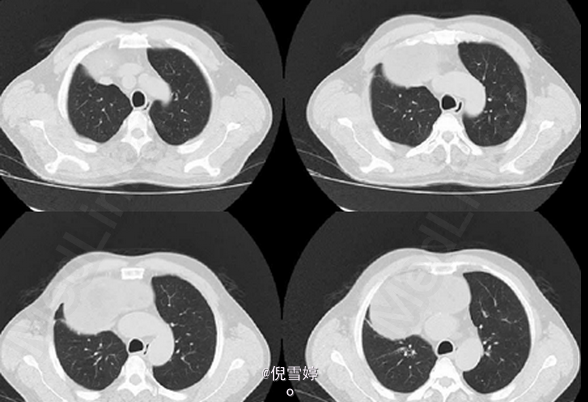

患者,男,49岁岁,因胸部不适2d就诊

患者除胸部不适外并无其他明显症状 辅查CT,右前纵隔囊性占位,多发脂肪样密度,病理检查良性

畸胎瘤 处理:手术切除